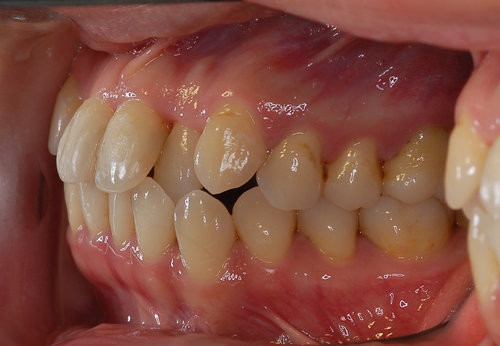

双颌前突给我们生活带来了很多不便和弊端,影响外貌美观之余,还会造成食物咀嚼不足,消化不良,影响身体健康,所以双颌前突必须经过矫正治疗。那么双颌前突矫正有副作用吗?下文为大家揭晓一下。

双颌前突

双颌前突矫正过程中可能会出现的小问题是牙齿脱矿和食物嵌塞。牙齿脱矿是指在矫正过程中,托槽周边或牙龈边缘位置出现的白垩色变化,一般是由于患者在矫正过程中没有仔细刷牙,没有维护好口腔卫生环境,致使牙齿表面的细菌产酸而使牙齿的颜色和实质发生变化。